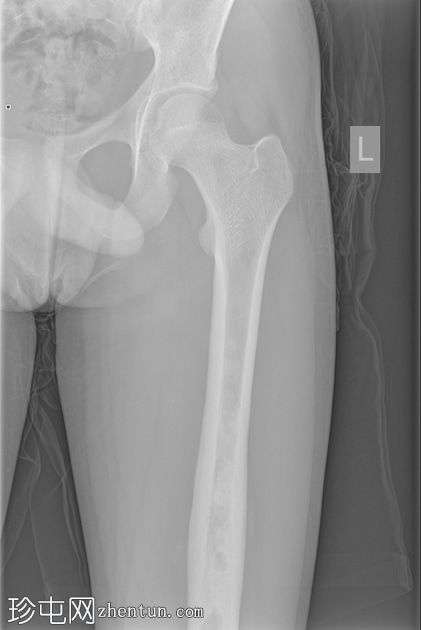

X光片

正面

左股骨中段可见边界不清的硬化区域,伴有宽阔的过渡区和虫蛀状外观。

邻近软组织可见小块钙化灶。无骨折或脱位。